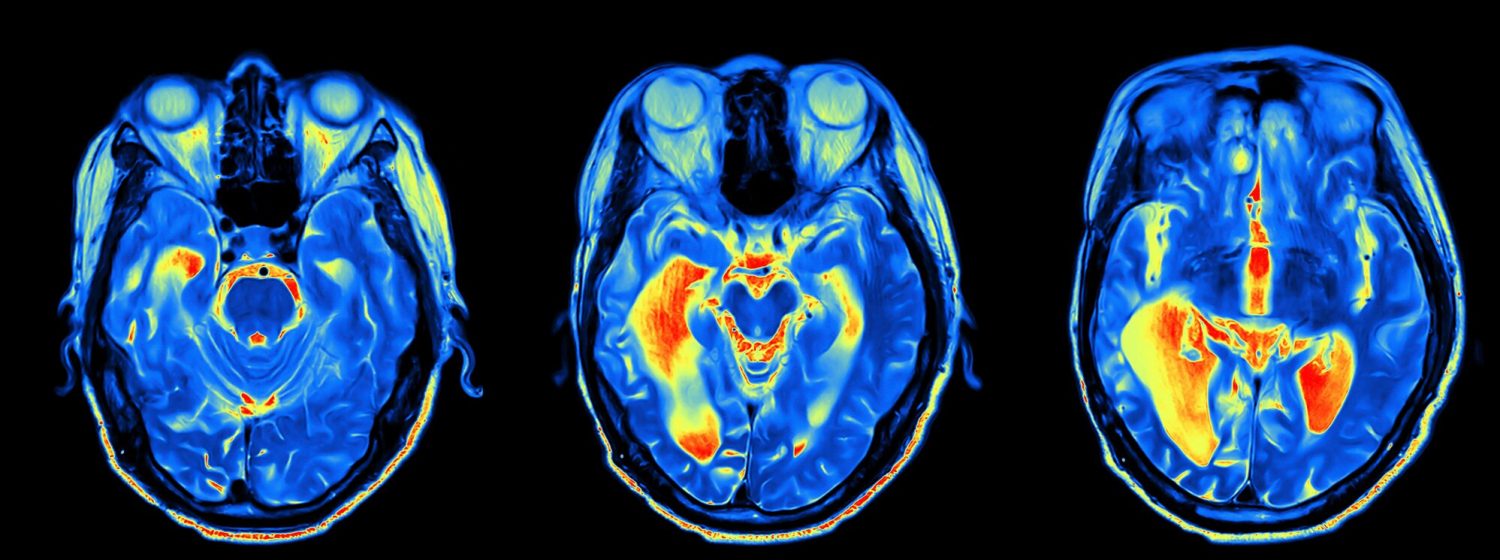

Применяется в диагностике этого заболевания и технологии искусственного интеллекта. Функциональная магнитно-резонансная томография (фМРТ) может дать представление о деятельности нейронов в мозге - но ее данные слишком сложны для анализа. В исследовании, проведенном в октябре 2020 года, американские ученые опубликовали результаты работы разработанных ими алгоритмов машинного обучения, анализирующих данные фМРТ. Первые результаты многообещающие: точность алгоритма была "такой же высокой, как и у других методов, или даже выше".

Английская компания Oxford Brain Diagnostics разрабатывает клиническую диагностическую платформу, основанную на собственном программном обеспечении для измерения кортикального дисбаланса мозга. В системе применяется программный анализ, базирующийся на использовании собственных алгоритмов компании. Этот метод анализирует характеристики коры головного мозга на основе данных МРТ-сканирования и, по словам разработчиков, позволяет заблаговременно, на много лет раньше, чем это возможно при использовании современных методов диагностики, диагностировать заболевания мозга.